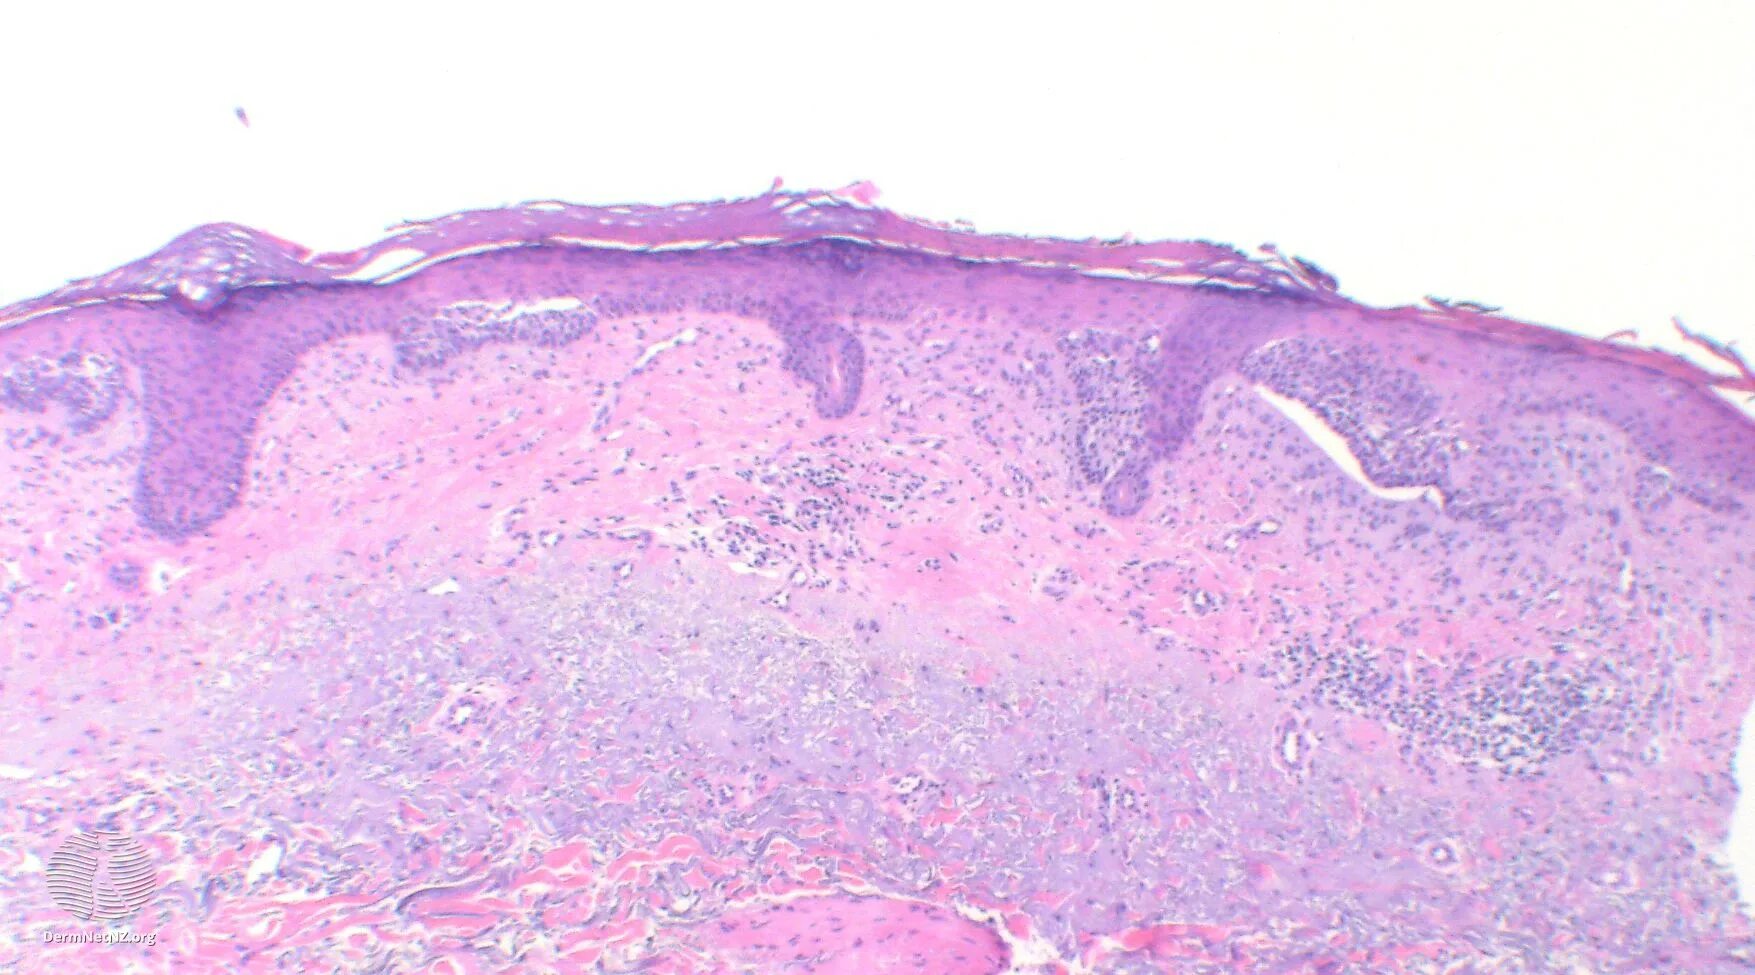

Гистология базалиома